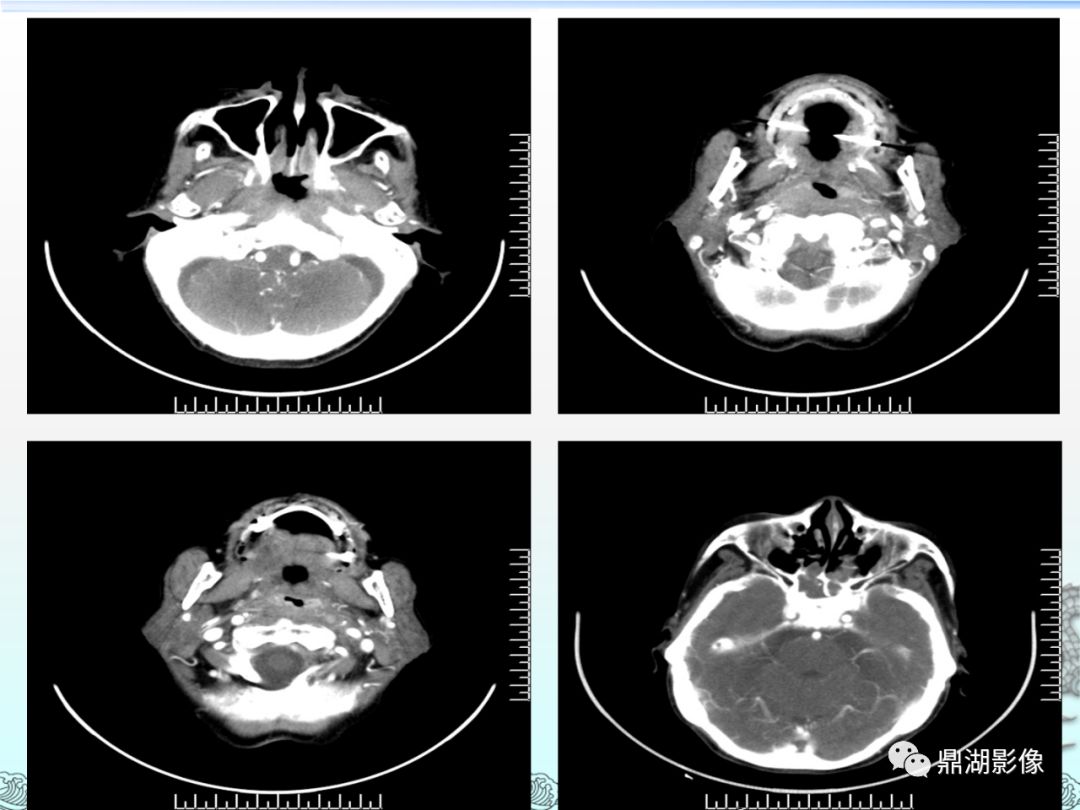

病例讨论鼻咽癌

图片尺寸3156x2332